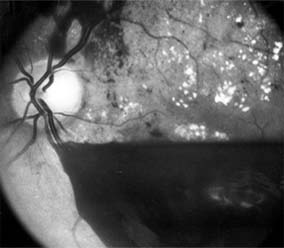

CENTRAL RETINAL VEIN OCCLUSION

Central retinal vein occlusion is a common and easily diagnosed retinal vascular disorder with potentially blinding complications. The patient presents with sudden painless loss of vision. The clinical appearance varies from a few small scattered retinal hemorrhages and cotton-wool spots (Figure 10-28) to a marked hemorrhagic appearance with both deep and superficial retinal hemorrhage, which may rarely break through into the vitreous cavity. Most patients who develop the disease are over 50 years of age, and more than half have associated cardiovascular disease. Predisposing factors and their investigation are discussed in Chapter 15. Chronic open-angle glaucoma should always be excluded (see Chapter 11).

Figure 10-28: Central retinal vein occlusion with extensive superficial retinal hemorrhage obscuring macular and optic nerve detail.

The two major complications associated with central retinal vein occlusion are reduced vision from macular edema and neovascular glaucoma secondary to iris neovascularization. Macular dysfunction occurs in almost all eyes with central vein occlusion. Although some eyes will show spontaneous improvement, most eyes will have persistent decreased central vision as a result of chronic macular edema. Nearly one-third of eyes with central retinal vein occlusion show significant retinal capillary nonperfusion on fluorescein angiography; one-half of these eyes will develop neovascular glaucoma.